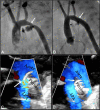

Transcatheter closure of patent ductus arteriosus (PDA) in premature infants is a feasible, safe, and an effective alternative to surgical ligation and may be performed with an implant success rate of 97%. Major procedural complications related to transcatheter PDA closure in extremely low birth weight (ELBW) infants are relatively infrequent (< 3%) ,but may be associated with a fatality if not optimally managed. Operators performing transcatheter PDA closures should be knowledgeable about these potential complications and management options. Prompt recognition and treatment are often necessary to avoid serious consequences. With strict guidelines on operator training, proctoring requirements, and technical refinements, transcatheter PDA closure in ELBW infants can be performed safely with low complication rates. This article summarizes the consensus guidelines put forward by a panel of physicians for the prevention and management of periprocedural complications of transcatheter PDA closure with the Amplatzer Piccolo Occluder in ELBW infants.